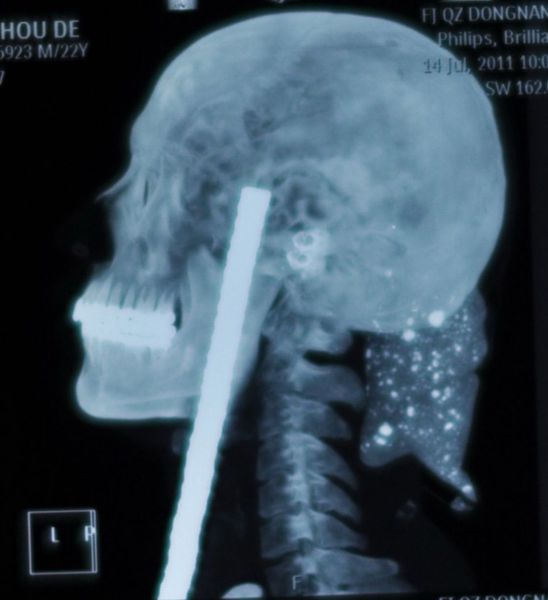

Eleven-year-old Chinese schoolboy Liu Cheong had a brush with death when his friend shot him in the head with a 16-inch arrow, according to numerous international media reports. The arrow entered his skull through the eye socket and lodged in the back of his head. Somehow, the boy was spared a fatal brain injury.